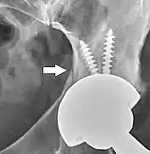

Loosening

On radiography, it is normal to see thin radiolucent areas of less than 2 mm around hip prosthesis components, or between a cement mantle and bone. These may indicate loosening of the prosthesis if they are new or changing, while areas greater than 2 mm may be harmless if they are stable.[31] The most important prognostic factors of cemented cups are absence of radiolucent lines in DeLee and Charnley zone I, as well as adequate cement mantle thickness.[32] In the first year after insertion of uncemented femoral stems, it is normal to have mild subsidence (less than 10 mm).[31] The direct anterior approach has been shown to itself be a risk factor for early femoral component loosening.[33][34][35]